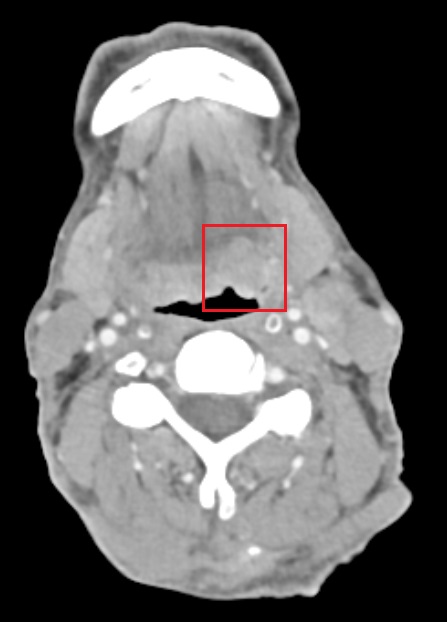

Λαρυγγεκτομή σε καρκίνο λάρυγγα με πρόσθια διάσπαση του θυρεοειδούς χόνδρου (T4a)

Ασθενής 51 ετών πρσήλθε με δυσφωνία με επίταση της συμπτωματολογίας